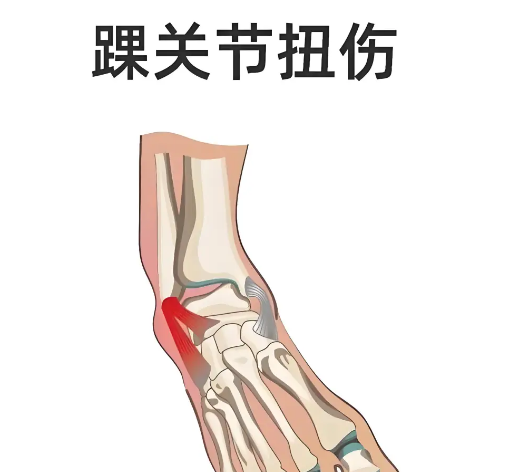

女人穿高跟鞋扭伤脚崴脚怎么办

**首先要采用冷敷。跟我们平常烫伤了一样,**时间要先进行冷敷,女人扭伤脚崴脚也是一样的道理。如果一旦发现扭伤脚崴脚了,一定不能在坚持走路,那样只会让脚的受伤程度更加的严重,一定要在*短的时间内进行冷敷。冷敷时,如果冷敷的东西比较多的话,那么可以整个受伤的脚进行冷敷,浸泡在冷敷水中,如果是冰...

脚扭伤了怎么做康复训练?

处理方法1 冷敷崴脚后,扭伤部位内部的小血管会破裂出血,使受伤部位形成血肿,一般要24小时左右才能停止出血和肿胀。而冷敷可使血管收缩,减少出血量,从而有效使受伤部位停止肿胀并消肿。处理方法2 热敷使用湿热手巾或者热水袋外敷于淤血肿胀部位,促进淤青部位血液循环,可以有效的减弱血肿情况。但崴脚后不...

脚扭伤了可以用热水泡脚吗?

24小时内冰袋冷敷,之后热水热敷,*好能喷点云南白药或者用涂擦正红花油,对脚扭伤的恢复很有帮助。另外,要注意多休息,这是*重要的一点。祝早日康复。脚扭伤后出现的浮肿,一开始用冷水外敷防止肿胀厉害,之后用热水外敷促进循环,加快消肿。指导意见:浮肿已经稳定了,可以用热水外敷,同时按摩促进血...